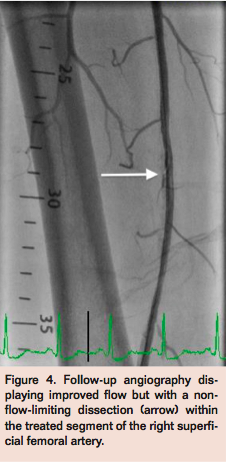

Access was obtained in the left common femoral artery (CFA) and a 7 Fr Pinnacle Destination sheath (Terumo) was positioned across the aortic bifurcation in the right CFA. Selective angiogram of the right lower extremity confirmed mid to distal 80% calcified stenosis of the right SFA (Figure 1), mild popliteal artery disease, and 2-vessel run-off into the right foot. A Grand Slam Wire (Abbott Vascular) was advanced across the right SFA lesion into the distal peroneal artery after anticoagulation with intravenous heparin. Intravascular ultrasound (IVUS) imaging (Volcano) was performed to determine the burden and character of the plaque, which confirmed a severe calcific and eccentric stenosis in the mid SFA (Figure 2). Rotational atherectomy with aspiration thrombectomy was performed using a Jetstream 2.1/3.0 atherectomy catheter (Bayer HealthCare) with four passes across the lesion, two with blades down and two with blades up (Figure 3). Follow-up angiography displayed improved flow but with a non-flow-limiting dissection within the treated segment of the right SFA (Figure 4). Repeat IVUS imaging confirmed an intimal flap consistent with post-atherectomy dissection (Figure 5). Nitinol-constrained balloon angioplasty was performed using a 5 mm x 80 mm over-the-wire Chocolate PTA balloon catheter (TriReme Medical) with a prolonged expansion over 2 minutes (Figure 6). Final angiogram demonstrated excellent angiographic result with brisk flow through the treated segment (Figure 7) and preserved run-off into the foot. Final IVUS imaging confirmed no residual dissection flap and improved luminal gain (Figure 8).